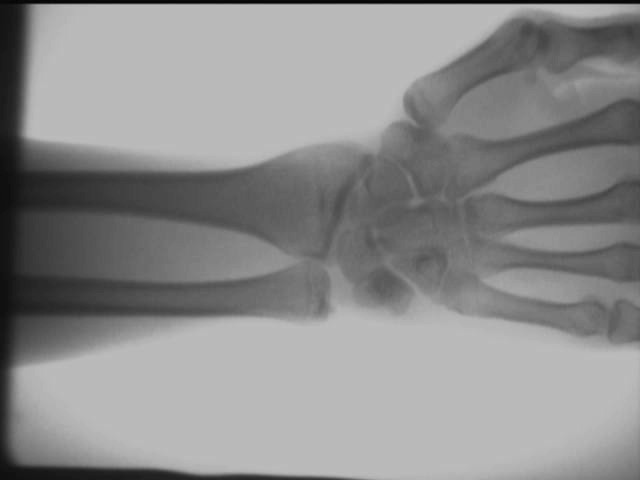

Diagramme d'effet de test sur site du détecteur de rayons X orthopédique

Effet d'articulation de la main et de la cheville

Les résultats des tests ci-dessus sont obtenus sur site à l'aide d'un AS-C200appareil à rayons X portable